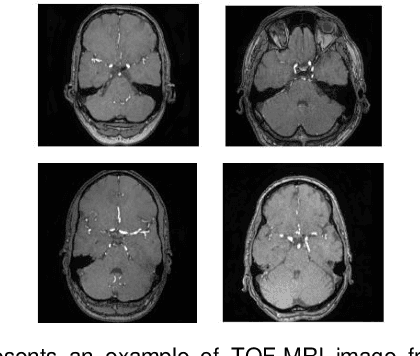

Abstract:Cardio-cerebrovascular diseases are the leading causes of mortality worldwide, whose accurate blood vessel segmentation is significant for both scientific research and clinical usage. However, segmenting cardio-cerebrovascular structures from medical images is very challenging due to the presence of thin or blurred vascular shapes, imbalanced distribution of vessel and non-vessel pixels, and interference from imaging artifacts. These difficulties make manual or semi-manual segmentation methods highly time-consuming, labor-intensive, and prone to errors with interobserver variability, where different experts may produce different segmentations from a variety of modalities. Consequently, there is a growing interest in developing automated algorithms. This paper provides an up-to-date survey of deep learning techniques, for cardio-cerebrovascular segmentation. It analyzes the research landscape, surveys recent approaches, and discusses challenges such as the scarcity of accurately annotated data and variability. This paper also illustrates the urgent needs for developing multi-modality label-efficient deep learning techniques. To the best of our knowledge, this paper is the first comprehensive survey of deep learning approaches that effectively segment vessels in both the heart and brain. It aims to advance automated segmentation techniques for cardio-cerebrovascular diseases, benefiting researchers and healthcare professionals.